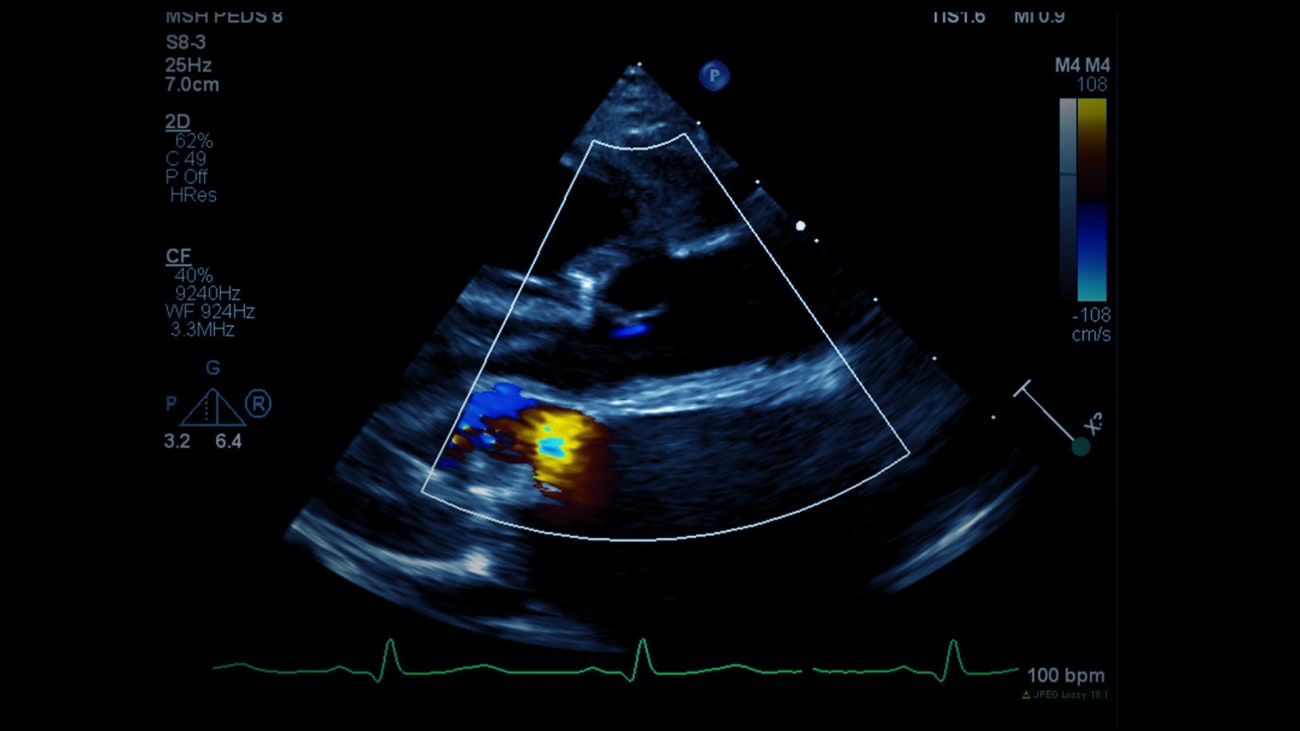

Liba, a 17-month-old girl, was diagnosed with congenital heart valve disease at birth. What sets her apart is that she not only had severe aortic valve stenosis, but also severe mitral valve regurgitation.

When she was just 2 weeks old, Liba’s parents brought her to Robert Pass, MD, Co-Director of the Mount Sinai Kravis Children's Heart Center, and Dr. Pass performed a cardiac catheterization with balloon aortic valvuloplasty. After the catheterization, Liba was left with mild aortic regurgitation, which is not uncommon after a valvuloplasty, but she was still able to go home. Her heart tolerated these residual defects early on, but as Liba grew, she began developing symptoms of heart failure. At approximately 15 months old, she began to appear weak and her growth plateaued.